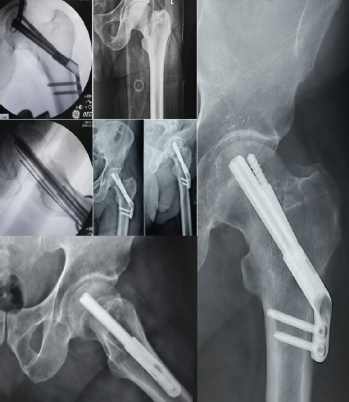

Case 3

A 54-year-old male presented with a Garden’s type III, Pauwel’s type III fracture after a low-energy injury. Closed reduction with minimal traction achieved near-anatomical alignment, followed by fixation with mild compression. Implant placement was satisfactory, with a good tip-apex distance and bi-cortical distal locking. At 3 months, complete union was seen with only minimal neck shortening (Fig. 2), and the patient regained full function. Younger age, good bone quality, and near-anatomical reduction were likely helpful in achieving this result in spite of a vertical fracture pattern (Pauwel’s type III).

Figure 2: Top left: Pre-operative, intraoperative C-arm images and immediate post-operative radiographs of Case 3; Bottom left and right: post-operative radiographs at 3 months

Case 4

A 24-year-old male sustained a high-energy injury with multiple pelvic fractures in addition to a displaced Garden’s type IV, Pauwel’s type III femoral neck fracture. Mild traction and valgus fixation with compression were achieved using the FNS, with adequate positioning of the blade and anti-rotation screw and bi-cortical distal locking. The patient was lost to follow-up as he was a native of West Bengal. However, we established contact with the patient after 12 months and his latest X-Rays showed that the fracture had united, but by 16 months AVN of the femoral head with secondary degenerative changes developed (Fig. 3). The displacement, comminution, high-energy mechanism, and possible early return to weight-bearing may have contributed to this complication, despite good implant placement and good bone quality.

Figure 3: (Case 4) Top right: Pre-operative 3D computed tomography image showing supero-postero-lateral neck comminution; Centre-right: Immediate post-operative AP radiograph; bottom row: intraoperative C-arm images; Top left: 16 months post-operative radiographs showing fracture union and osteoarthritis hip changes secondary to AVN